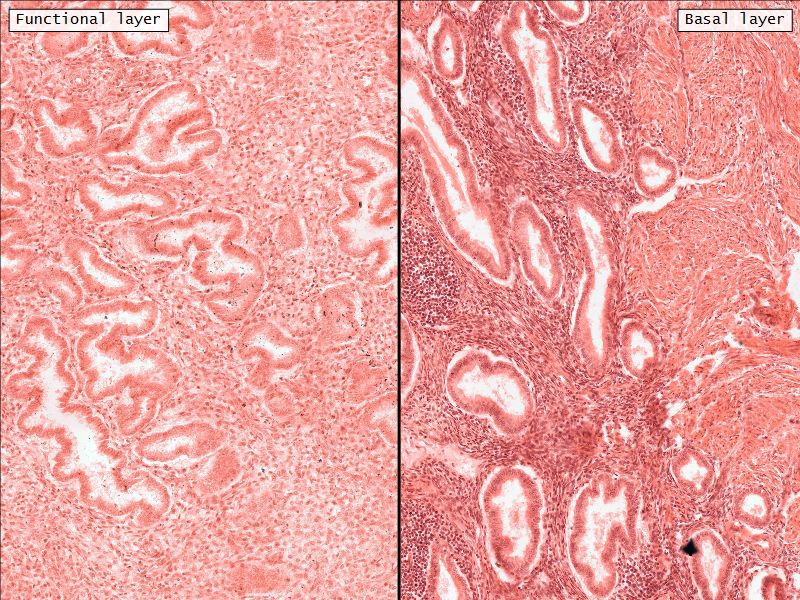

- Two layers

- Thick superficial functional

- Deeper basal layer

- Separation indistinct

- Functional layer

- Basal layer

Functional layer

- Thick superficial layer

- Cyclic monthly hormonal changes

Basal layer

- Thin deeper layer

- Preserved during menstruation